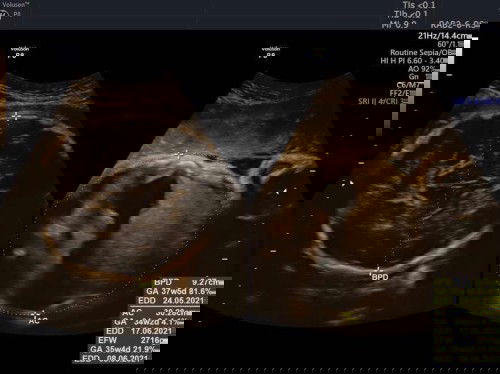

Saya hamil 38week ini udah pembukaan 1 dan udah keluar darah, tapi belom merasakan mules/kontraksi/sakit pinggang bener” gaada keluhan apa”. Kira” pembukaan 1-10 itu nunggu waktu berapa lama ya bun? Dan baiknya ke RS sekarang atau nunggu ada kontraksi dulu ya? Maaf saya hamil pertama, mohon bantu jawab ya bun🙏🏻 #ingintahu #firstbaby #jangandibully #bantu_jawab